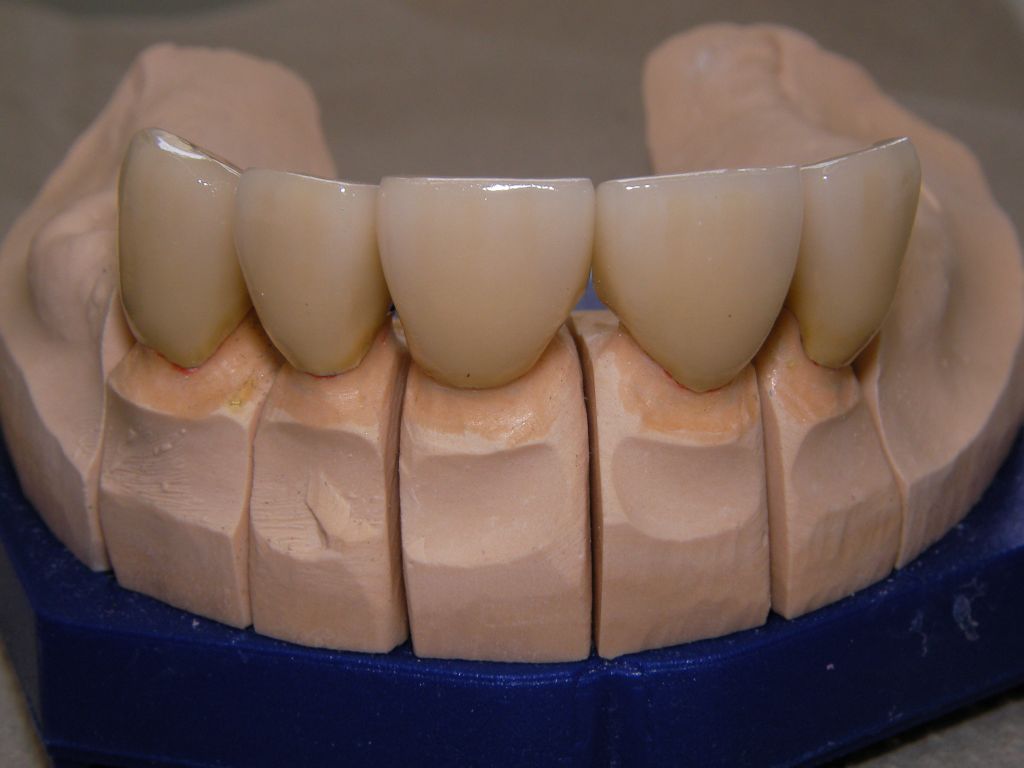

Links das Bild zeigt das Metallgerüst, das später mit Keramik verblendet wurde. Um eine einfache Mundhygiene ebenso wie eine hohe zahntechnische Präzsion zu erreichen, wurden risikobehaftete Verblockungen minimiert. Rechts die Ästhetikeinprobe bei entspannter Oberlippe. |

Links Bilder des Oberkiefers, rechts des Unterkiefers. Die Arbeit wurde von dem Dentallabor "Heitmeyer Zahntechnik", Osnabrück, gefertigt. Dem Labor ist hier für die hervorragende Arbeit zu danken, dem Patienten für die Freigabe der Bilder! |